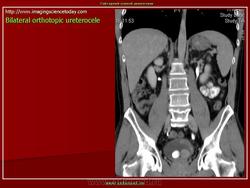

Продолжение.

Приложения:

1.u.slayd173.jpg2.u.slayd174.jpg3.u.slayd175.jpg